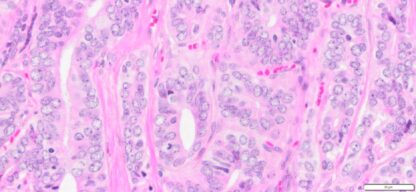

| Tissue | Pathology Diagnosis | Gender/ Age (year) | %Tumor Area | Tumor Grade | TMN/Stage | IHC data |

| Prostate | Human Prostate Adenocarcinoma, Acinar type, Gleason score 9 (4+3) | Male/53 | 55% | II | NA | NA |

Human tissue was fixed in formalin immediately after excision and embedded in paraffin. The tissue sections were 5 µm in thickness and mounted each on positively charged glass slides.